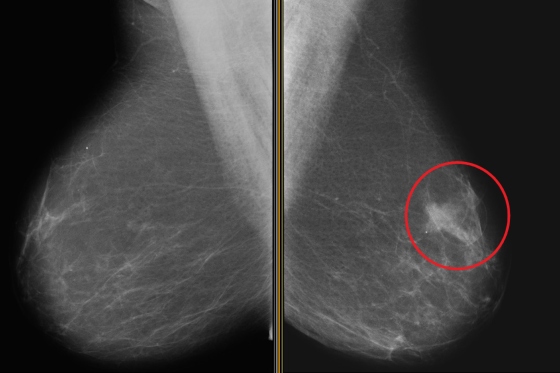

In stabilirea diagnosticului de carcinom ductal in situ, mamografia este standardul de aur. Prin mamografie se observa microcalcificarile specifice casting-like, adica asemenea unei structuri ramificate liniare, lungi, fine. Alteori, apare o opacitate de tesut moale, cu sau fara calcificarile specifice.

Tipul calcificarilor poate orienta, de asemenea, diagnosticul: cele liniare sunt mai frecvente in carcinomul ductal in situ de tip comedo, iar cele granulate se intalnesc mai ales in carcinomul ductal in situ de tip non-comedo.

In aproximativ 8% din cazuri, carcinomul ductal in situ apare doar ca masa sau asimetrie, uzual fara calcificari, ceea ce ingreuneaza diagnosticul. Este important de mentionat, insa, ca modul de distributie a calcificarilor pe mamografie poate subestima, in unele cazuri, gradul extinderii reale a bolii, lucru evidentiat ulterior la examenul histopatologic.